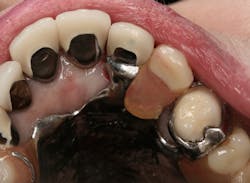

Figure 2: Intaglio surface of existing PFM retrofit preparation

The intaglio surface of the PFM crown contained the preexisting dentin core preparation. The decision was made to prepare the surface to receive the intraoral portion of the post rather than completely remove the remaining dentin (figure 2). This was done to facilitate a smooth retrofit between the remaining root structure and intaglio crown surface as well as to maximize bonding surface area between segments.